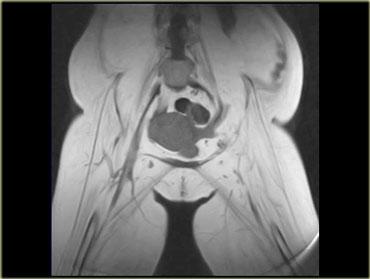

Viêm cơ trong bệnh mạch máu collagen

Bệnh nhân có bệnh lý mạch máu collagen nền có thể phát triển viêm cơ,

chẳng hạn như viêm khớp dạng thấp, lupus ban đỏ hệ thống (SLE), bệnh mô liên kết hỗn hợp và hội chứng Sjogren.

Ví dụ, như ở bệnh nhân SLE này, tổn thương có thể rất khu trú (ảnh mặt phẳng coronal, chân phải, khoang cơ khép) hoặc dạng nốt.

Một dạng viêm cơ nốt là viêm cơ tăng sinh khu trú, đây là thể ít gặp nhất.

Dạng này có thể gặp không chỉ trong bệnh mạch máu collagen mà còn trong u lympho.

Tổn thương do viêm cơ đôi khi không thể phân biệt được với bản thân u lympho, và cần sinh thiết để xác định chẩn đoán.

Hình bên trái là một bệnh nhân khác với viêm cơ nốt khu trú, trông giống như bất kỳ khối nào khác trên chuỗi xung T1W, T2W và sau tiêm thuốc tương phản từ.

Với tiền sử u lympho, có thể gợi ý viêm cơ nốt khu trú, nhưng không có gì mang tính quyết định từ các hình ảnh này.

Mối liên hệ giữa viêm cơ và bệnh ác tính tiềm ẩn vẫn còn gây tranh cãi, và tần suất của mối liên hệ này chưa được xác định rõ ràng.

2 loại ung thư có mối liên hệ với viêm cơ: ung thư buồng trứng và u lympho không Hodgkin

(hình bên trái là bệnh nhân với, thật kỳ lạ, ung thư tuyến giáp di căn).

Viêm cơ có thể xuất hiện trước bệnh ác tính (như trong hội chứng cận u), điều này không có nghĩa là cần tầm soát ác tính thường quy

ở bệnh nhân biểu hiện viêm cơ.